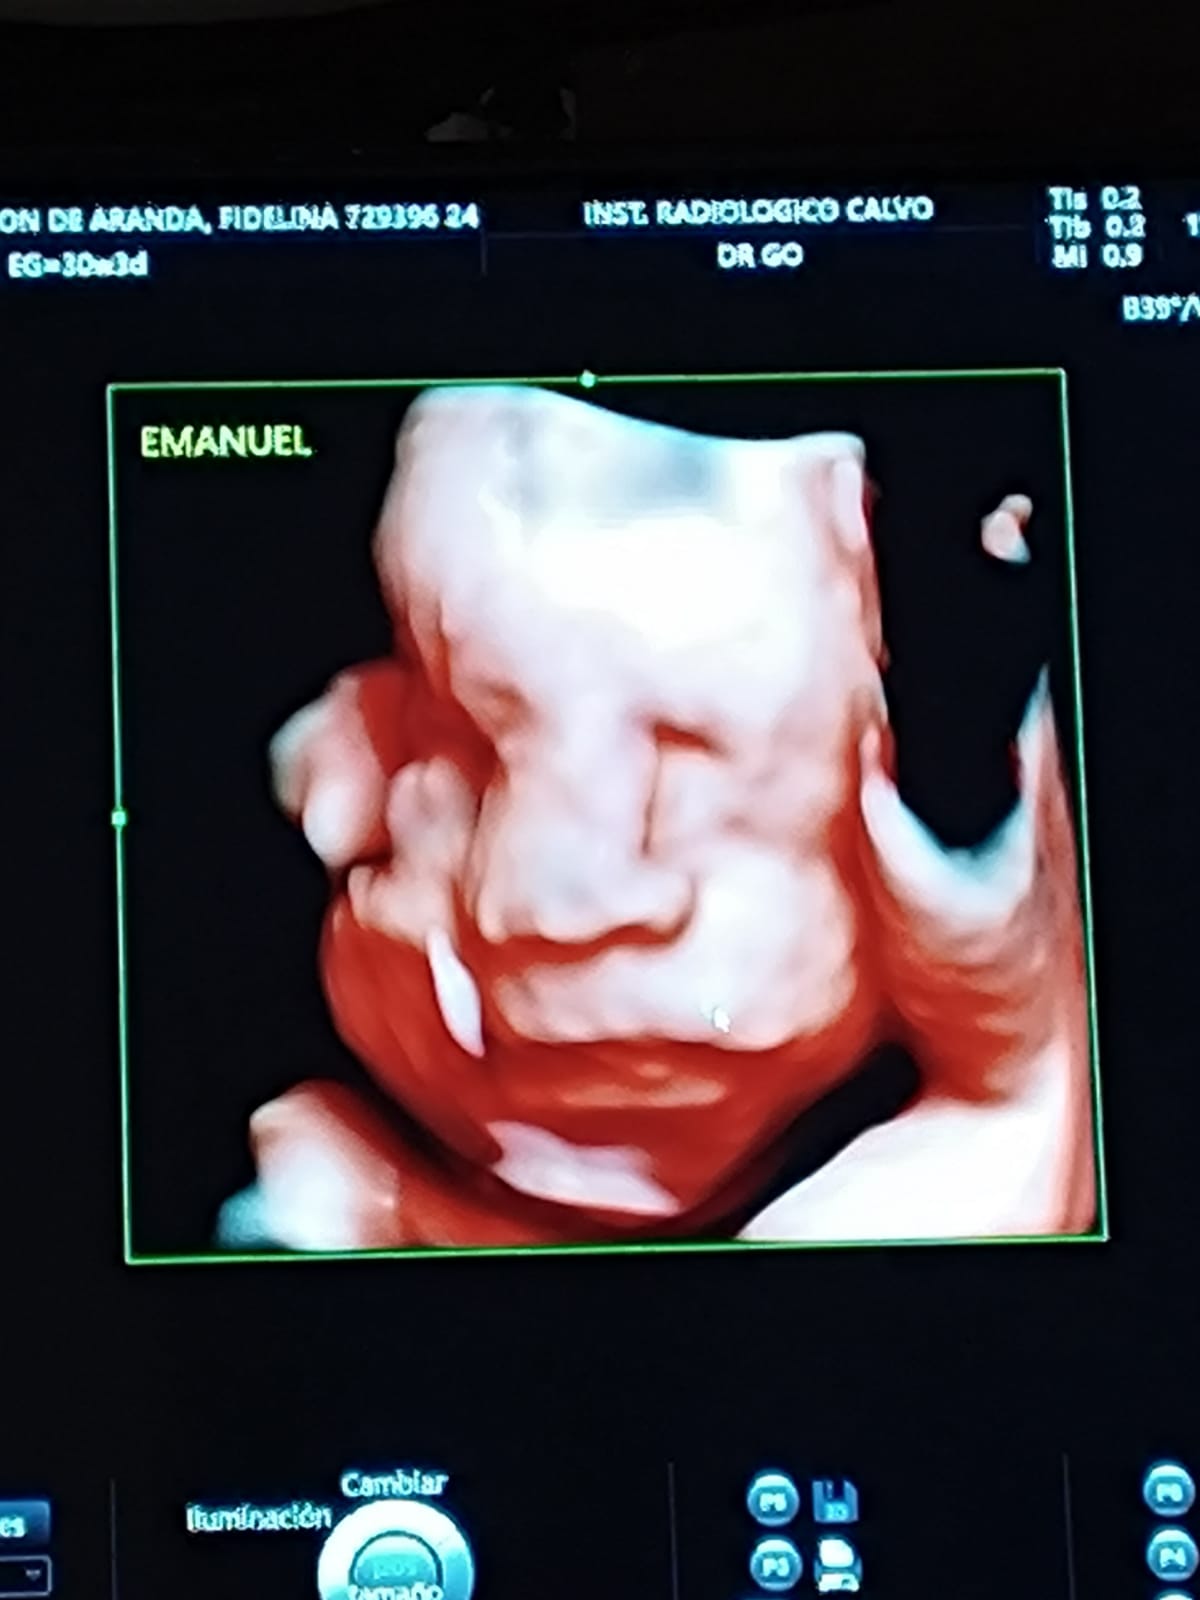

El cuadro fue manejado mediante controles seriados de ecografía Doppler y monitoreo evolutivo semanal, logrando la normalización progresiva del crecimiento fetal a partir de la semana 22 y una evolución favorable de los tres fetos en los controles posteriores.

A las 30 semanas y 4 días de gestación, se decidió interrumpir el embarazo mediante cesárea de urgencia debido a una complicación materna por hipertensión arterial, pese al tratamiento profiláctico con ácido acetilsalicílico (AAS) 150 mg. La intervención se realizó de manera oportuna priorizando la seguridad materno-fetal.